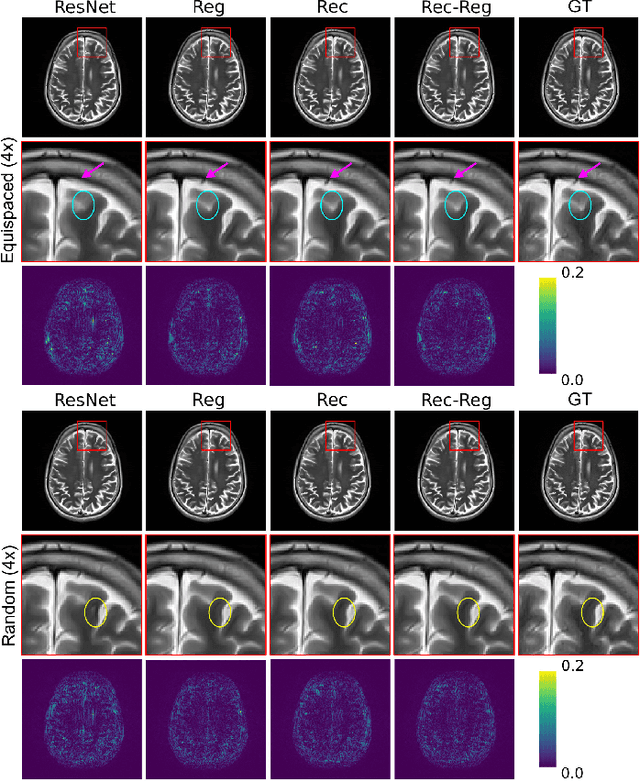

Abstract:In clinical practice, magnetic resonance imaging (MRI) with multiple contrasts is usually acquired in a single study to assess different properties of the same region of interest in human body. The whole acquisition process can be accelerated by having one or more modalities under-sampled in the $k$-space. Recent researches demonstrate that, considering the redundancy between different contrasts or modalities, a target MRI modality under-sampled in the $k$-space can be more efficiently reconstructed with a fully-sampled MRI contrast as the reference modality. However, we find that the performance of the above multi-modal reconstruction can be negatively affected by subtle spatial misalignment between different contrasts, which is actually common in clinical practice. In this paper, to compensate for such spatial misalignment, we integrate the spatial alignment network with multi-modal reconstruction towards better reconstruction quality of the target modality. First, the spatial alignment network estimates the spatial misalignment between the fully-sampled reference and the under-sampled target images, and warps the reference image accordingly. Then, the aligned fully-sampled reference image joins the multi-modal reconstruction of the under-sampled target image. Also, considering the contrast difference between the target and the reference images, we particularly design the cross-modality-synthesis-based registration loss, in combination with the reconstruction loss, to jointly train the spatial alignment network and the reconstruction network. Experiments on both clinical MRI and multi-coil $k$-space raw data demonstrate the superiority and robustness of multi-modal MRI reconstruction empowered with our spatial alignment network. Our code is publicly available at \url{https://github.com/woxuankai/SpatialAlignmentNetwork}.